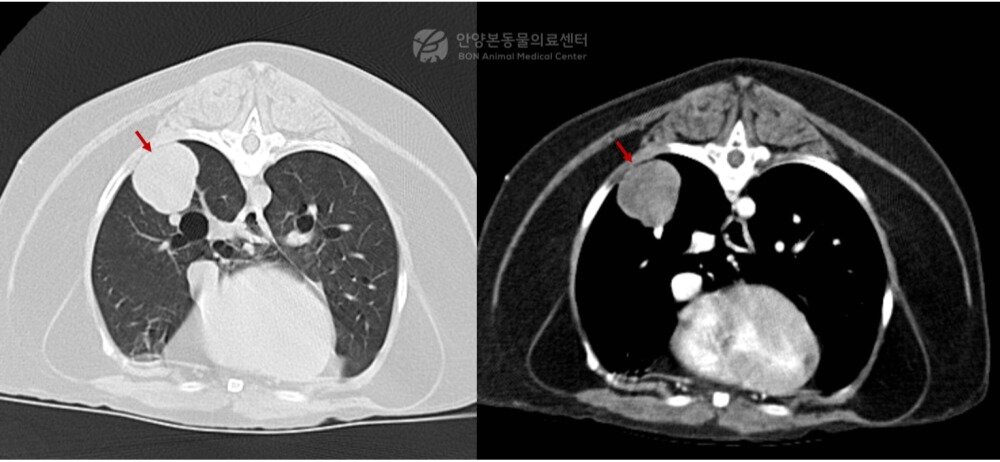

본문 이미지 - 폐 CT 검사 결과 발견된 종괴(본동물의료센터 제공) ⓒ 뉴스1

폐 CT 검사 결과 발견된 종괴(본동물의료센터 제공) ⓒ 뉴스1